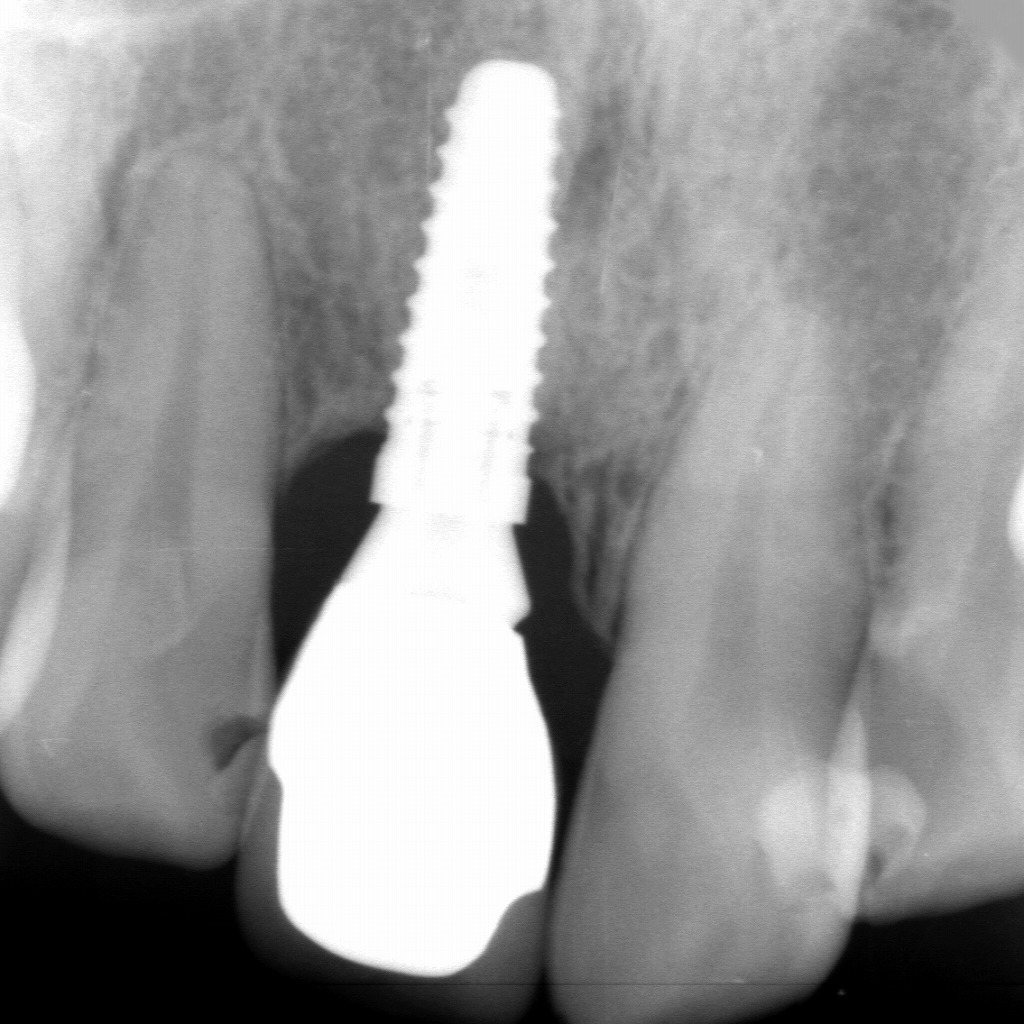

■ インプラント最終上部構造装着後のレントゲン

このX線画像は、右上顎1番のインプラントに最終上部構造(セラミッククラウン)が装着された後の状態を示しています。

中央に見える白く明瞭な構造がインプラント体で、その上部に高いX線不透過性(白く写る)を示す**最終補綴物(クラウン)**が確認できます。

■ 画像から読み取れるポイント

1. インプラント周囲骨の良好な成熟

インプラント体の周囲には骨が均一に存在し、

骨吸収はほとんど認められません。

特に前歯部に重要な頬側骨が、治療計画どおり再生されていることが推察できます。

2. インプラントの安定したポジション

インプラントの長軸は隣在歯の軸と調和しており、

上部構造の審美性・機能性に適した位置に維持されています。

3. 上部構造の適切な適合

クラウンのフィニッシュライン周囲に異常なギャップやセメントの過剰残留は認められず、

補綴物の適合も良好と判断できます。

4. 隣在歯との調和

左右の天然歯の歯根膜腔、根尖状態にも異常所見はなく、

インプラントが周囲組織に影響を与えていない安定した状態が確認できます。

■ 臨床的まとめ

- GBRを伴う難症例であったが、

インプラント周囲骨の成熟・審美性・機能性が良好に獲得できている完成形レントゲンである。 - 上部構造装着後のレントゲン所見として、

長期的経過観察へ移行できる安定した状態が示されている。